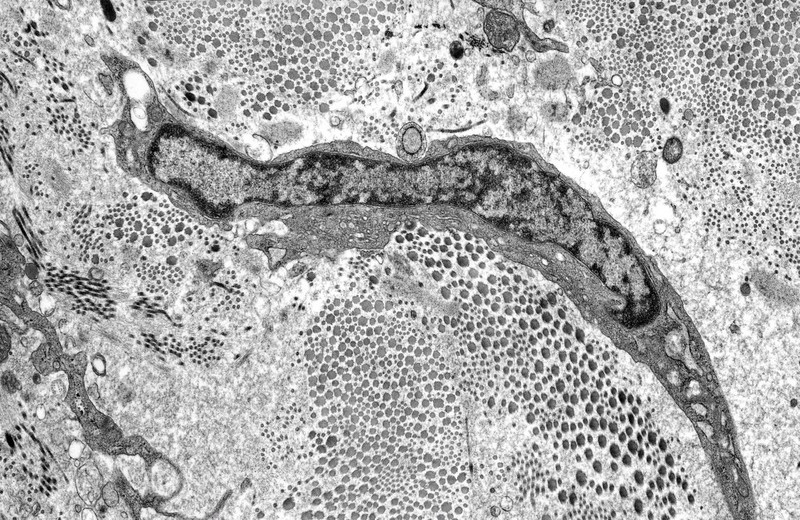

Credit: Fibroblast in ulcerated scleral stroma. Rob Young. Source: Wellcome Collection.

Credit: Fibroblast in ulcerated scleral stroma. Rob Young. Source: Wellcome Collection.